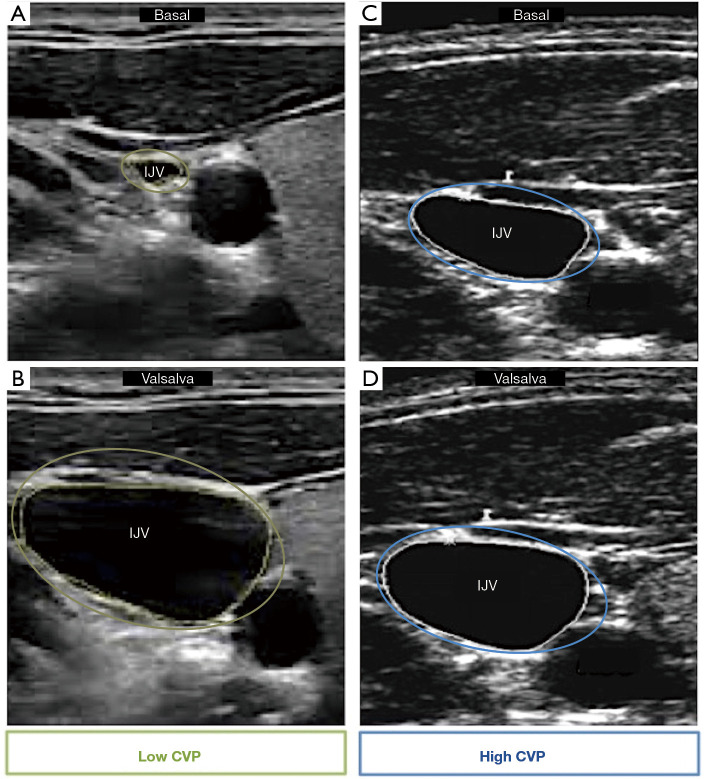

Background and objective: Congestion is a key determinant in the evolution of patients with heart failure (HF), leading to higher rates of emergency visits, hospital admissions and even mortality. Both clinical and subclinical congestion have been associated with a worse prognosis, hence the importance of its correct detection, characterization and treatment. Multiparametric assessment with ultrasound imaging, lung ultrasound (LUS) and venous Doppler analysis, has emerged as a very informative and accessible diagnostic tool in HF patients throughout their evolution. This review aims to provide a practical approach for the implementation of these techniques as well as a comprehensive summary of their prognostic and therapeutic applications in specific clinical settings.

Key content and findings: Ultrasound imaging for congestion detection and management is increasingly convening attention in HF scientific literature. Observational and randomized studies exhibit consistent and reproducible results where greater degrees of congestion have been strongly associated with worse clinical short- and long-term outcomes both in acute and chronic HF. On the other hand, ultrasound imaging helps adjusting diuretic therapy with more frequent and robust evidence regarding LUS than venous Doppler analysis.